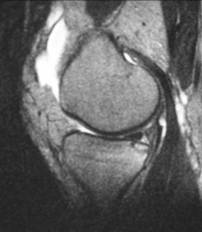

Bone bruise

n “microtrabecular” fracture

n No cortical break or instability

n Heals with rest

n Often associated with other injuries